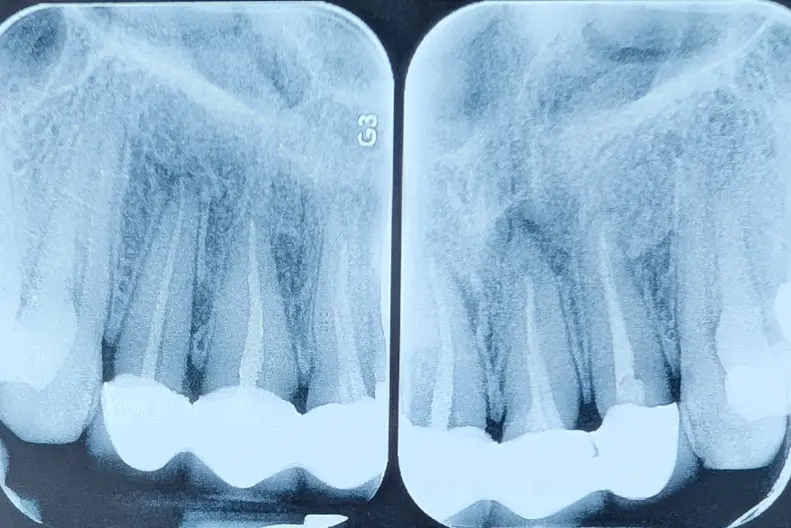

🟦 Insight — ارزیابی واقعی دندان فقط بعد از برداشتن روکش

ارزیابی دندان زیر روکش اسپلینت شده

در بیمارانی که روکش قبلی آنها می‌بایست خارج شود، تا زمانی که روکش برداشته نشود، وضعیت واقعی دندان—حجم تاج، پوسیدگی، ترک—قطعاً معلوم نیست. این یک قانون همیشگی‌ست.

اما وقتی چند دندان به‌صورت اسپلینت کنار هم قرار گرفته‌اند، این عدم‌قطعیت چند برابر می‌شود؛ چون افرادی که دندان‌ها را بی‌دلیل اسپلینت می‌کنند، خیلی احتمال دارد که دندان‌های Hopless را هم برای نگه‌داشتن، به دندان‌های سالم اسپلینت کنند و ظاهر کار گول‌زننده می‌شود.

بیمار برای تعویض چهار روکش متصل به هم مراجعه کرده بود.

ارزیابی دندان همیشه پس از برداشتن روکش است—اما در روکش‌های اسپلینت، باید آمادگی بیشتری برای هر سناریویی داشت.